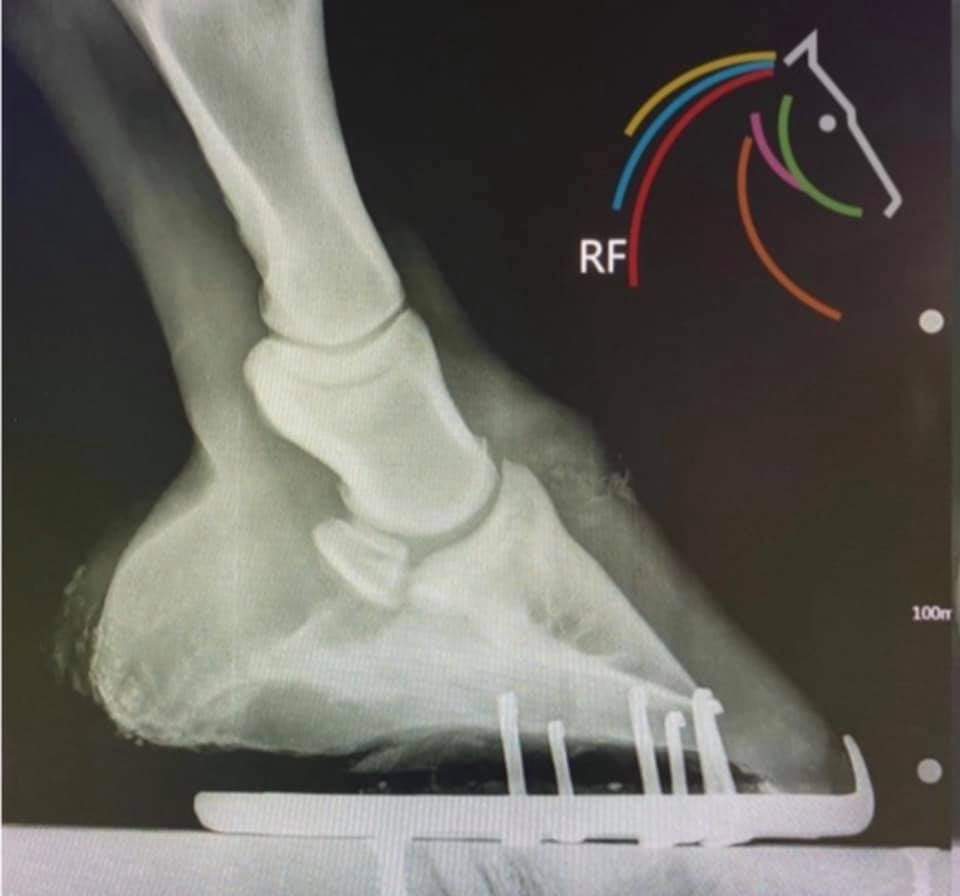

HOVBENET BARA HALVA HOVEN

Hovbenet finns bara i främre delen av hoven. Det betyder att den bakre halvan är fylld med mjuk, elastisk och flexibel stötdämpande vävnad.

Bild 2: Grå delar är skelett, vitt sidobrosk, gult elastiska putan.

Den naturliga balanspunkten i hoven visas av den vita pricken på bild 2, den befinner sig direkt under leden. Idealiskt ska det vara lika mycket hov framför den som bakom. Den “inre” hoven är i balans, men den “yttre” hoven (hovkapseln) är inte i balans. Hovkapseln skulle behöver verkas annorlunda för att uppnå balans.

Bild 1 är en hov med bättre balans.